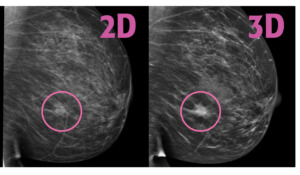

Not all mammograms are created equal. Some facilities offer 3D mammograms (also called tomosynthesis). If you can find a facility near you that offers this, schedule your appointment there. Also, some facilities use locator stickers which helps the radiologist read the image.